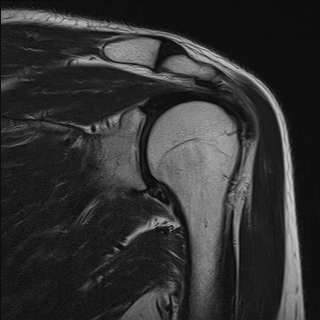

±Ø»ó°Ç³»Ãø Á¾´Ü¸é°Ë»ç¿¡¼­ ±Ø»ê°Ç ºÎÂøºÎÀÇ  ÀÛÀº ÆÄ¿­°ú Á¡¾×³¶ ºÎÁ¾ÀÌ °üÂûµÊ(±×¸² 2, 3).

±Ø»ó°Ç ¿ÜÃø Á¾´Ü¸é°Ë»ç ½Ã Á¡¾×³¶ ºÎÁ¾ÀÌ °üÂûµÊ(±×¸² 4).